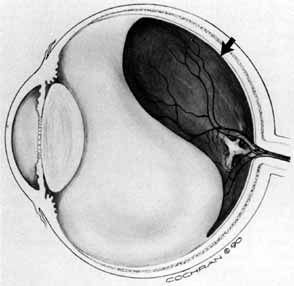

Some authors have commented on the importance of a posterior vitreous detachment in the pathogenesis of a macular hole.34,35 It is difficult to determine the vitreoretinal relationship preoperatively, even with careful slit-lamp evaluation. OCT testing can sometimes be helpful. However, the vitreomacular relationships are more accurately determined intraoperatively with use of oblique intraocular illumination and by noting the effect of gentle tractional forces on the macula during the vitrectomy. In some cases, what was thought to be a posterior vitreous separation preoperatively was actually found to be a large, optically empty space (Fig. 3).